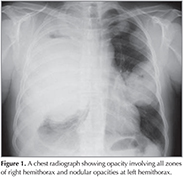

?A 43-year old male patient was admitted with dyspnea and chest pain. On physical examination the breath sounds were markedly diminished at right hemithorax and he had bilateral gynaecomastia. He was a smoker and his smoking history was 22 pack years. A chest radiograph showed opacity involving all zones of right hemithorax and nodular opacities at left hemithorax (Figure 1). A thorax computed tomography (CT) revealed a mass lesion occupying almost all right hemithorax and multiple masses in the left hemithorax. There was also pleural effusion and compression atelectasis at right hemithorax. Laboratory studies revealed a normal complete blood count and serum biochemistry. The erythrocyte sedimentation rate was elevated. Since he was a young patient, had bilateral multiple masses at thorax CT and also had gynaecomastia, a germ cell tumor was suspected and serum β-HCG level was analyzed. The serum β-HCG level was found as elevated: 4261 mIU/mL (normal less then 2.0). Positron emission tomography (PET)-CT revealed pathologic 18 FDG uptake at mass lesions in both hemithorax and mediastinal lymph nodes (Figure 2). Positron emission tomography and ultrasonography showed no gonadal involvement. A bronchoscopy was performed and an endobronchial lesion at the apical segment of right upper lobe was observed. A definitive diagnosis was not achieved by pathologic examination of biopsy specimen, bronchoscopy was repeated and samples were taken by cryobiopsy. Tumor consisted of solid sheets of uniform large tumor cells (Figure 3). Tumor cells were positive with P63 and β-HCG (Figure 4). Keratin 5/6, TTF-1, PLAP and AFP were negative in tumor cells. Mucine carmin staining was negative. We didn't observe syncytiotrophoblast and cytotrophoblast. Our case was β-HCG secreting nonsmall cell lung carcinoma. Since the patient was inoperable, a chemotherapy protocol was started.